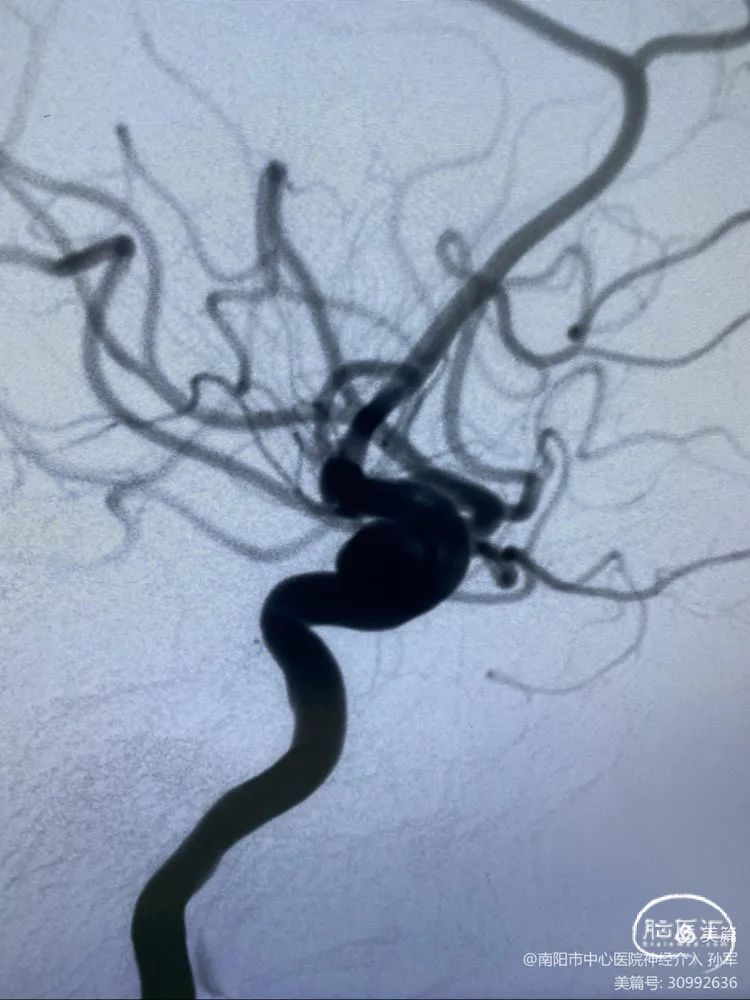

5

遂回收支架,重上marksman至M2远端。

再次释放支架,打开良好,支架头端导丝位置良好。

病例总结

血流导向装置释放后短缩很厉害,其中间导丝会前行很远,因此支架导丝远端需要放置在平直的血管内,释放支架时需要注意支架远端导丝的位置。曾有专家报告过支架导丝远端刺破大脑中动脉分叉部引起严重并发症的病例,需大家重视。